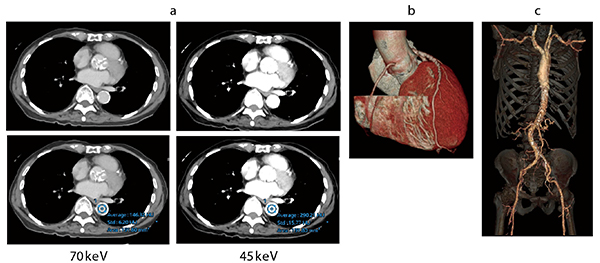

症例2 大動脈弁狭窄症(心臓Volume Scan+Spectral Scan)

経カテーテル大動脈弁留置術(TAVI)術前の計測、アクセスルートの確認目的。eGFRが23と腎機能が悪く、造影剤を極力減らした検査が求められた。造影剤は40mLで、Volume Scan+Spectral Scanで撮影した。大動脈3D画像(c)はCT値を上昇させるため45keVの画像を使用したが十分評価可能であった。

また、Aquilion ONE / PRISMでは、dual energy(DE)撮影技術である“Spectral Imaging System”を用いた低エネルギー画像の描出によって、造影剤量の低減が可能になっている。浦島主任部長は、「経カテーテル大動脈弁留置術(TAVI)では、術前に心臓血管外科から心臓と大動脈の情報が求められますが、腎機能が悪い患者が多く造影剤量を抑える必要があります。そのため従来は心臓のみを撮影していましたが、Aquilion ONE / PRISMではSpectral Imaging Systemによる低エネルギー画像の描出で造影剤の投与量を落とすことができ、従来の心臓CTの造影剤量で大動脈まで撮影可能になりました。情報量を落とさずに造影剤腎症のリスクを抑えた検査が可能になっています」と述べる。心臓CTの造影剤40mLで大動脈撮影まで可能になっている。